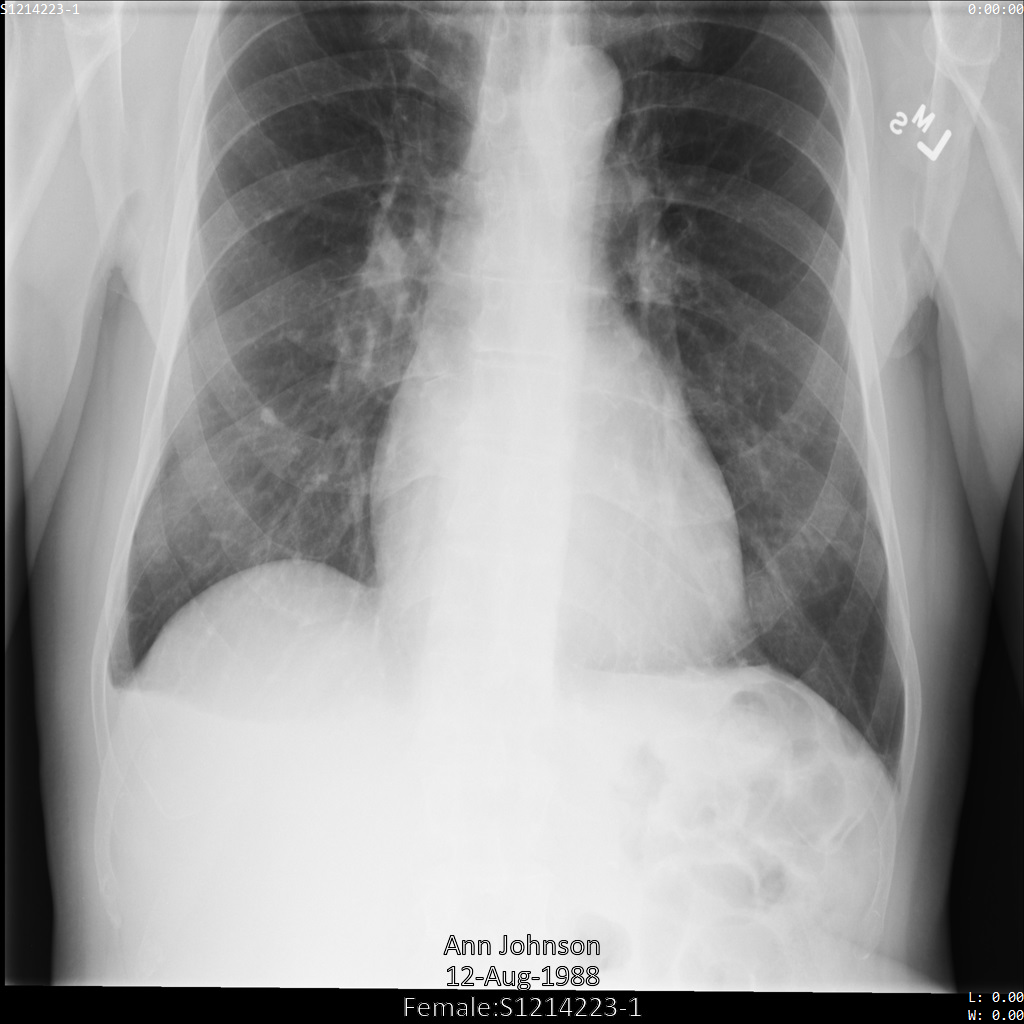

Depois de enviar a imagem para a Cloud Healthcare API, a imagem aparece da seguinte forma. Embora os metadados apresentados nos cantos superiores da imagem tenham sido ocultados, as informações de saúde protegidas (PHI) incorporadas na parte inferior da imagem permanecem. Para também remover o texto incorporado, consulte o artigo Ocultar texto incorporado em imagens.